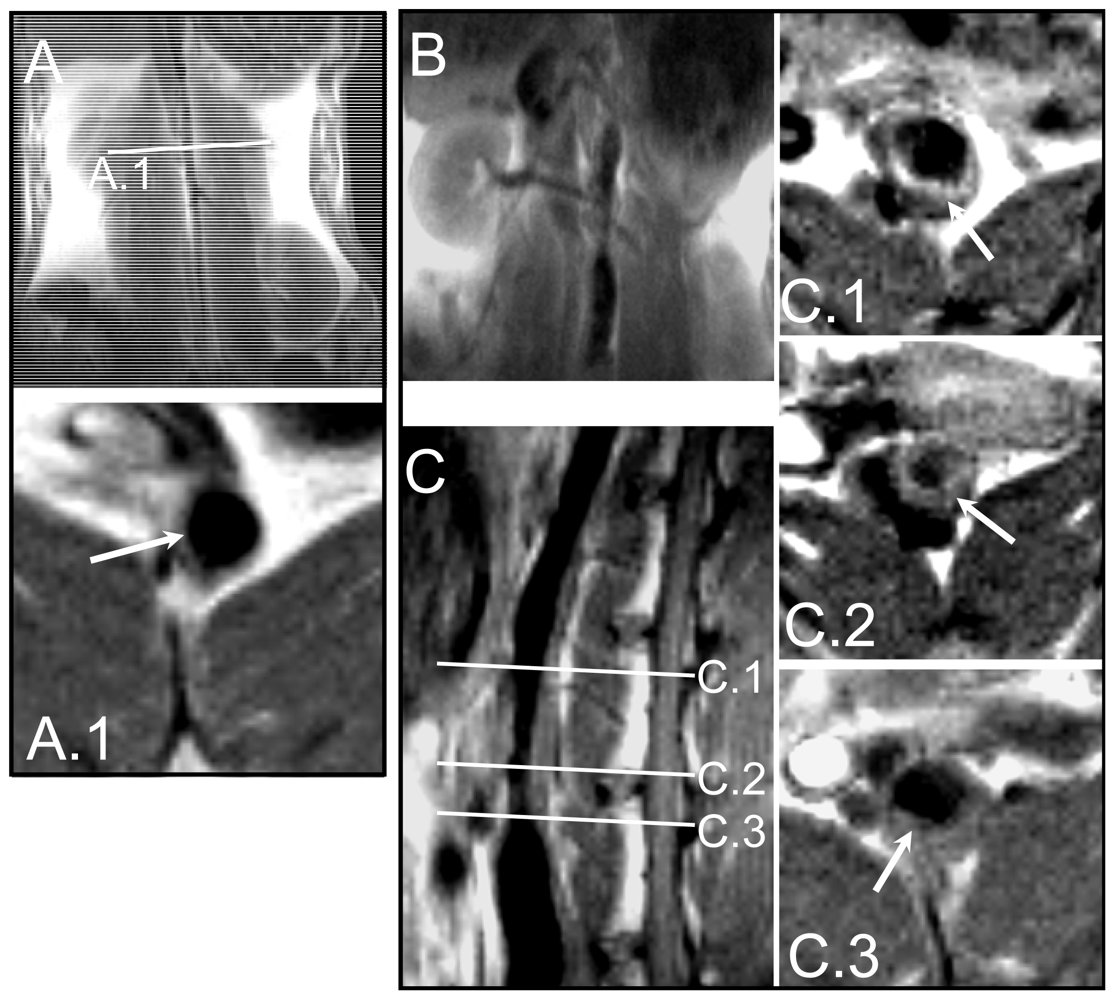

2.1. Rabbit model of Atherosclerosis

3.1. Animal Model

3.2. Magnetic Resonance Imaging